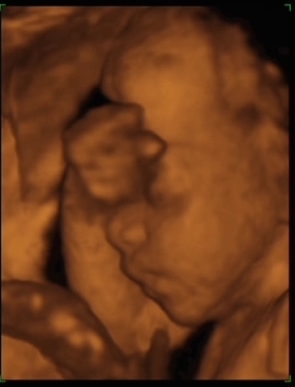

Panka 22 hét 4 naposan. 4D Genesisben készült.

Kép